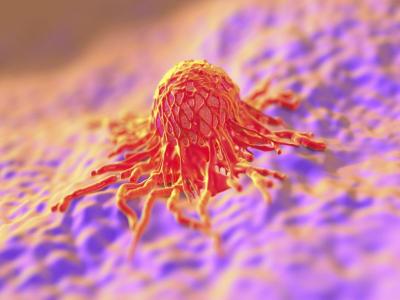

कुछ प्रकार के कैंसर को रोकने में मदद मिल सकती है कई अध्ययनों से संकेत मिलता है कि खट्टे फल कुछ कैंसर के विकास के जोखिम को कम करने में मदद कर सकते हैं। इनसे फेफड़ों के कैंसर के विकास का जोखिम कम हो सकता है।